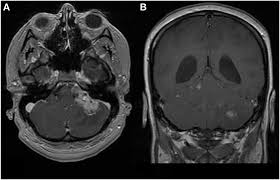

Mri of an atypical teratoid rhabdoid tumor (atrt) in the brain. Symptoms of atrt may include the following: Background cancer is the second leading cause of death in children, after accidents. An atypical teratoid rhabdoid tumor (atrt) is a very rare, aggressive tumor of the central nervous system, occurring mostly in the cerebellum, the part of the brain that controls movement and balance, or the brain stem, the part of the brain that controls basic body functions. Still, cancer is the second leading cause of death in children younger than 15 years old, after accidents.

Atypical Teratoid Rhabdoid Tumor Atrt Boston Children S Hospital from www.childrenshospital.org The external malignant rhabdoid tumor has specific characteristics, i.e. The other symptoms depend on where in the body the cancer. Mri of an atypical teratoid rhabdoid tumor (atrt) in the brain. Our family's journey with atrt. Ninety percent of patients with these tumors are age 2 or younger. As his mom, lori, explains, his survival has come at a cost. Atrt is a very difficult tumor to cure, and, unfortunately, the outcomes remain poor. Headache, which is often worse in the morning or improves after vomiting

Because atypical teratoid/rhabdoid tumor is fast growing, signs and symptoms may develop quickly and get worse over a period of days or weeks. 6 originally described in the 1980s, atrt has been. In infants you may see an increase in the size of the head, and for patients of all ages the most common symptoms are: A rhabdoid tumor that grows in the kidneys and soft tissues is called a malignant rhabdoid tumor (mrt). As his mom, lori, explains, his survival has come at a cost. Mri of an atypical teratoid rhabdoid tumor (atrt) in the brain. Like a lottery nobody wants to win, we suddenly found ourselves in a category of cancer so small, so. The most common symptoms of rhabdomyosarcoma are pain, a swollen lump, or both. Still, cancer is the second leading cause of death in children younger than 15 years old, after accidents. An atypical teratoid rhabdoid tumor (at/rt) is a rare tumor usually diagnosed in childhood. They may also appear in the kidneys of infants. Babies and cancer q&a by erin breese, m.d. It tends to show up in the arms, legs, or trunk.